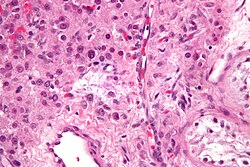

| Seminoma | fried egg cells | fried egg-like cells (central nucleus, clear cytoplasm) with squared-off nuclear membrane, nucleoli, lymphocytic infiltrate, granulomata, syncytiotrophoblastic giant cells[5] |

D2-40 | Dysgerminoma = female version of this tumour | |